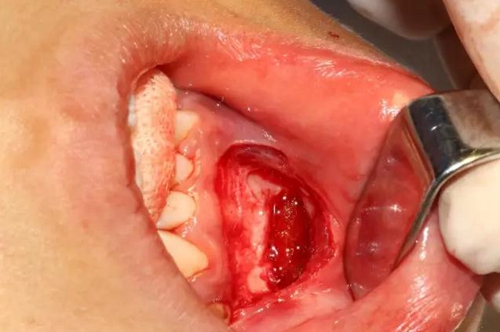

去除含牙囊壁

創(chuàng)口處理

創(chuàng)口內(nèi)置入膠質(zhì)銀明膠

關(guān)閉創(chuàng)口、對位縫合